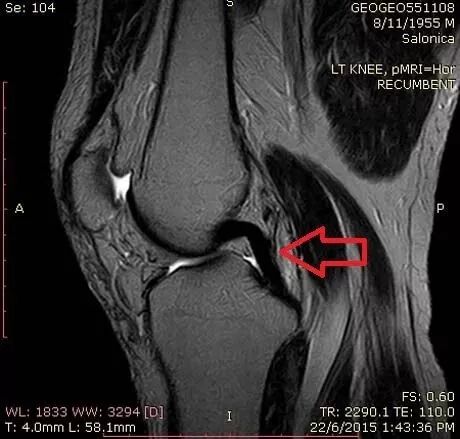

但是,有时我们却能看到“两条”后交叉韧带?

图2 膝关节正矢状位 MRI FS-T2WI 图像,红色箭头所指处可见两条低信号带,并列走行